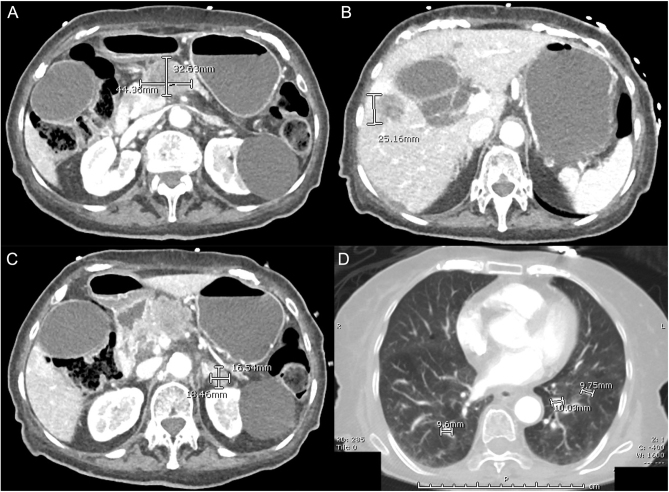

Summary: Diabetic ketoacidosis (DKA) is a complication of diabetes mellitus (DM) that can theoretically occur in people of any age. While DKA can typically be the first presentation of type 1 DM in younger people, a first presentation is rare in older adults. Pancreatic cancer often manifests with new DM or hyperglycaemia, but very rarely as DKA. We report a case of an 89-year-old woman who was incidentally diagnosed with DKA during workup for an unwitnessed fall. Her DKA was promptly managed, and she was subsequently diagnosed with metastatic pancreatic cancer. Given the advanced stage of her malignancy, the multidisciplinary team consensus was for a palliative approach. She passed away on day 10 of the admission. To our knowledge, this is the first report of a first DKA presentation as a manifestation of pancreatic cancer in an adult aged over 70 years. To date, there is no effective screening test for pancreatic cancer in the general population. However, new-onset DM in the appropriate context might indicate the need for further evaluation. While it is possible that unresectable tumours are identified, earlier diagnosis of DM with pancreatic cancer may facilitate more timely management, including earlier advanced care planning.